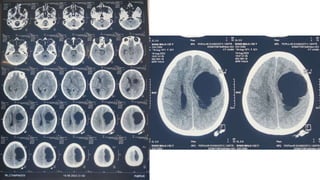

CT Scan of the head

CT Scan ofthe head

• #41 Plain CT scan of Head revealed Smooth bordered non calcified cystic lesion with single septation in left frontoparietal region with density similar to CSF with crowding of adjacent sulcus & gyrus, effacement of adjacent lateral ventricle and slight midline shifting Rest of the brain parenchyma, bony calvaria is normal. No extracalvarial lesion is visible.

• #43 MRI of brain T1WI multiple axial sections showing a well defined fairly large lesion measuring 7.5cm * 4.5cm in diameter, smooth bordered homogenously hypointense lesion in left frontoparietal region with intensity similar to CSF. There is crowding of adjacent sulcus & gyrus and effacement of adjacent lateral ventricle and slight midline shifting Rest of the brain parenchyma is normal. No extracalvarial lesion is present.

• #44 T2WI shows the lesion is homogenously hyperintense.

• #47 FLAIR image shows the lesion is homogenously hypointense

• #48 No restriction; nearly identical to ventricles Diffusion restricted –pheriphery –neoplasm Centrally-radiation necrosis

• #49 Contrast enhanced axial MRI shows there is no contrast uptake by the lesion and also there is no ring enhancement

• #50 Contrast is not uptaken by the lesion.